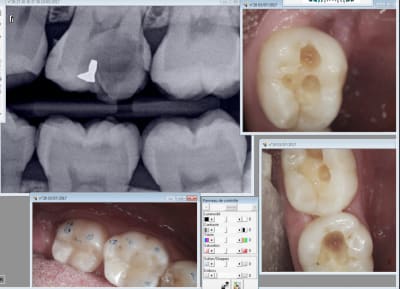

Tous les dossiers patients sont électroniques et la Sécu a accès sans avoir à demander au compte rendus, radios photos, et réalise des contrôles fréquents.

Donc avant de faire une couronne, c est radio, et photo de la dent. Toutes les étapes sont enregistrées et le moindre composite ou anesthésie doit être enregistré au dossier patient pour traçabilité.

C est un travail de documentation très important intégré dans les tarifs.

Ca ca vaut 0 en Suède because pas de digue je suppose. C'est comme en France en fait. -)